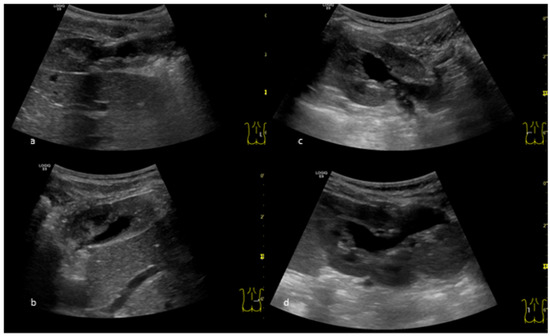

2. Case Presentation